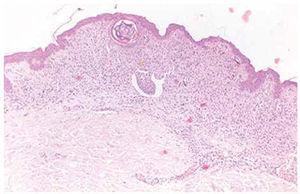

En los casos 5 y 6 no existían criterios concluyentes de nevo congénito. Los pacientes recordaban tener las lesiones pigmentadas desde hacía años, pero no desde la infancia. En el caso 5, la paciente tenía como antecedente un nevo displásico en otra localización. La lesión pigmentada incluida en el estudio correspondía a un nevo melanocítico intradérmico con componente lentiginoso suprayacente, con características diagnósticas de nevo compuesto. En ambos casos se observaron estructuras vasculares linfáticas en la dermis adyacente a la lesión, que contenían melanocitos en su luz en forma de agregados irregulares o adheridos al endotelio (figs. 4 y 5). Por último, el caso 8 (que correspondía a un nevo intradérmico común), presentaba masas polipoides de melanocitos que protruían en la luz de los vasos linfáticos situados en el seno de la proliferación melanocítica dérmica.

Fig. 4.--Invasión de vasos linfáticos adyacentes y subyacentes al nevo. (Hematoxilina-eosina, ×40.)